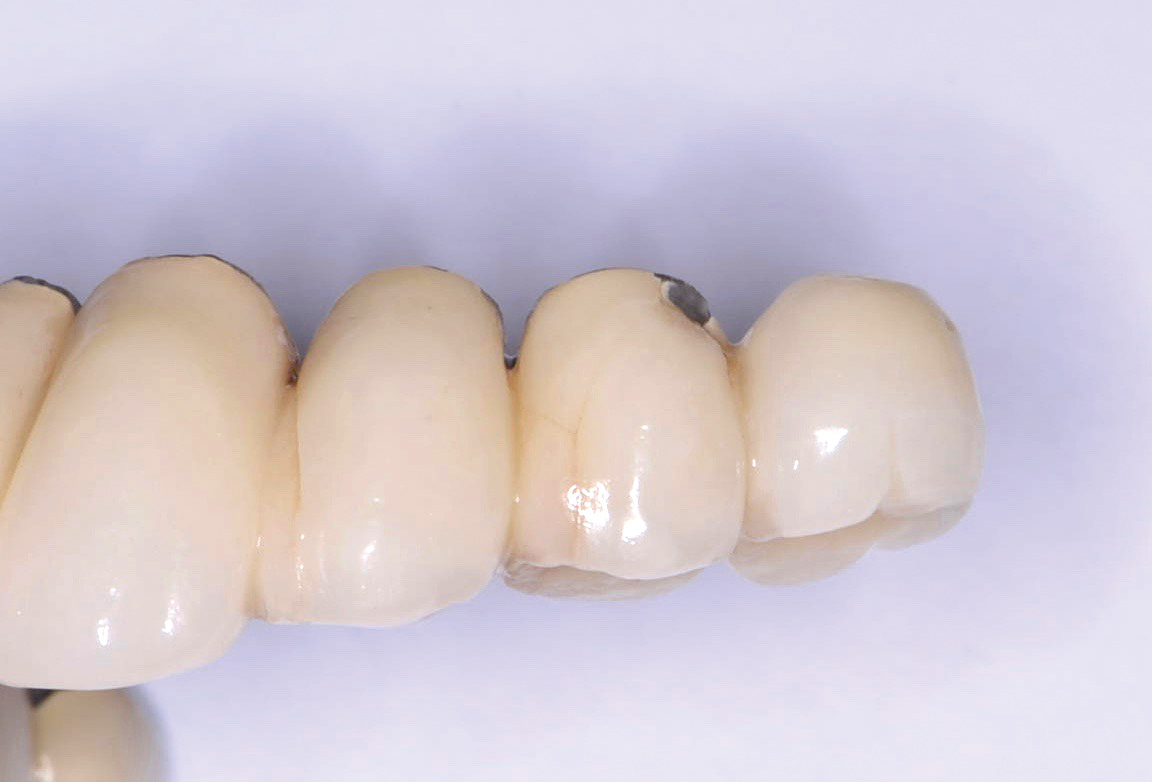

Fig 7. Ill-fitting milled abutment obtained from a third-party vendor and not from the manufacturer.

Figure 7

The use of third-party vendors for prosthetic components should be avoided.10 Third-party components (Figure 7) typically do not fit to the same standards as the manufacturer’s recommendations and can, thus, both weaken the screw connection before the screw is even placed in function and introduce micromotion that may lead to fracture of the implant or the screw/prosthesis, or crestal bone loss.11,12